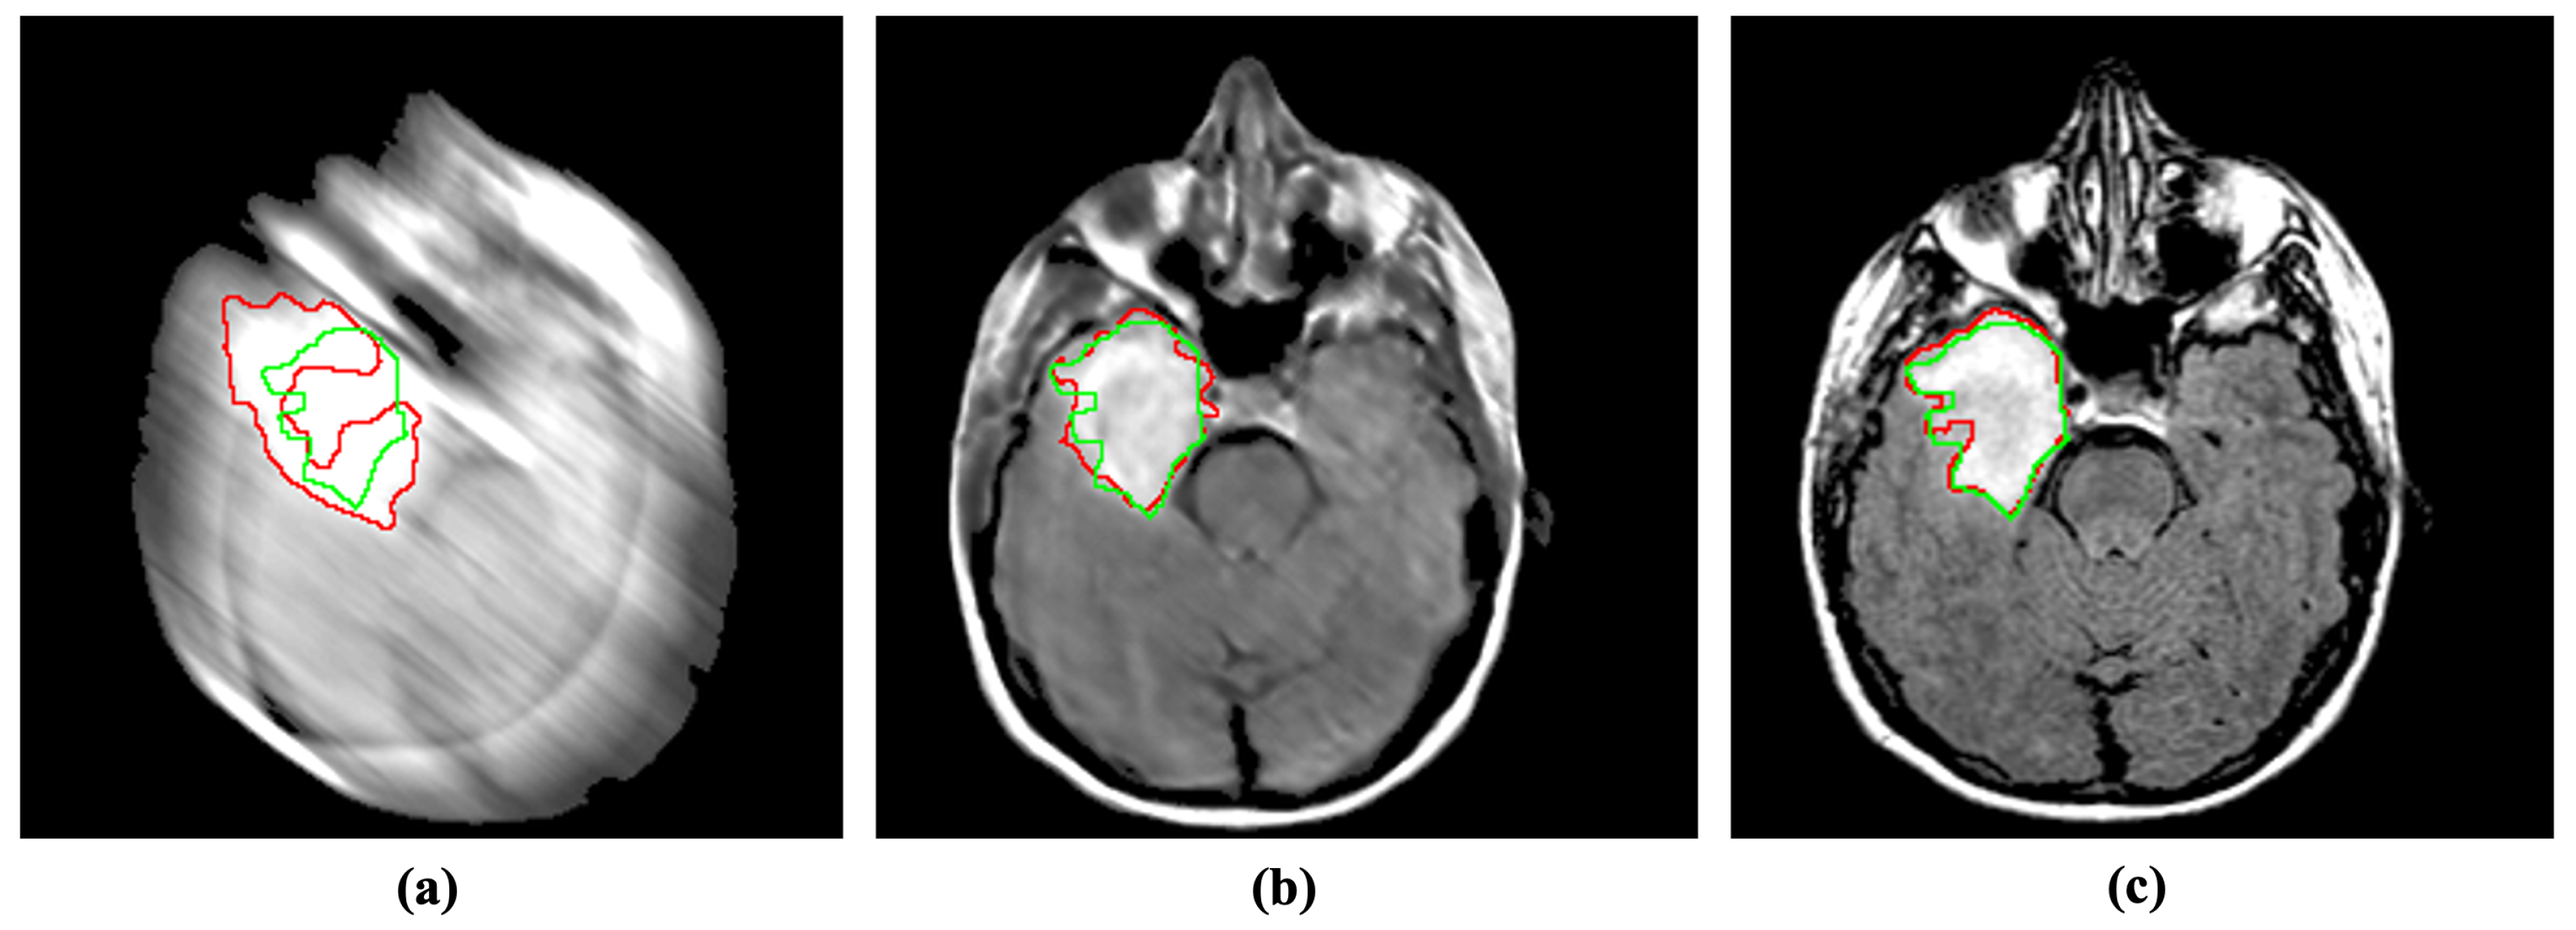

4.2.1. Segmentation

Abnormality segmentation is considered among the most prominent CAD applications in medical image analysis. Despite having substantial real-world implications, medical image segmentation suffers from blind-motion blur. As Figure 6 illustrates, the existing segmentation methods’ performance can drastically deteriorate by blind-motion blur. A robust deblurring method can help segmentation methods in improving their performance. Here, we evaluated the SOTA U-net architecture inspecting the impact of blurs in segmentation on MRI images.

Figure 6.

Incorporating the proposed method for deblurring medical images can improve medical image segmentation performance. The red and green regions represent the area segmented by the deep model and the actual (ground-truth) affected region. (a) Blurry image + U-Net [36]. (b) Deblurred image obtained by proposed method + U-Net [36]. (c) Reference image + U-Net [36].